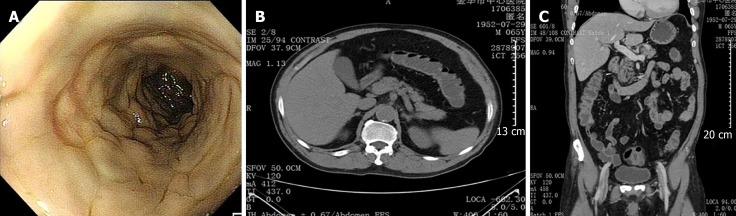

A 64-year-old man was referred to our department from his primary hospital because of abdominal pain, diarrhea, and fever for almost 10 d. Computed tomography showed colon wall thickening, with threadlike calcifications in the mesenteric vein in the transverse colon. Colonoscopy revealed purple-blue mucosa with multiple ulcers in the ascending and transverse colon. Biopsy showed thickening and calcification of the vein walls, perivascular and mucosal collagen degeneration, and amyloidosis. The patient had been consuming Chinese medicinal liquor, mainly that made from gardenia fruit, for 10 years. Based on these results, a diagnosis of MP with amyloidosis was made. After conservative treatment, the patient's discomfort subsided and he was followed closely. The use of Chinese herbal medicine was suspected to play a role in the pathogenesis of MP.

一名64岁男性因腹痛、腹泻和发热近10天从基层医院转诊至我科。计算机断层扫描显示结肠壁增厚,横结肠肠系膜静脉有丝状钙化。结肠镜检查显示升结肠和横结肠黏膜呈紫蓝色,有多处溃疡。活检显示静脉壁增厚、钙化及血管周围和黏膜胶原变性,还有淀粉样变性。该患者饮用中药酒(主要由栀子果实制成)已有10年。基于这些结果,诊断为伴有淀粉样变性的MP。经过保守治疗,患者的不适症状缓解并接受密切随访。怀疑使用中草药在MP的发病机制中起作用。

The clinical manifestations of MP are nonspecific. Recognition of its typical imaging findings, including multiple calcifications on computed tomography and purple-blue mucosal discoloration on colonoscopy, is vital.

MP的临床表现不具有特异性。认识其典型的影像学表现至关重要,包括计算机断层扫描上的多处钙化以及结肠镜检查时黏膜呈紫蓝色。